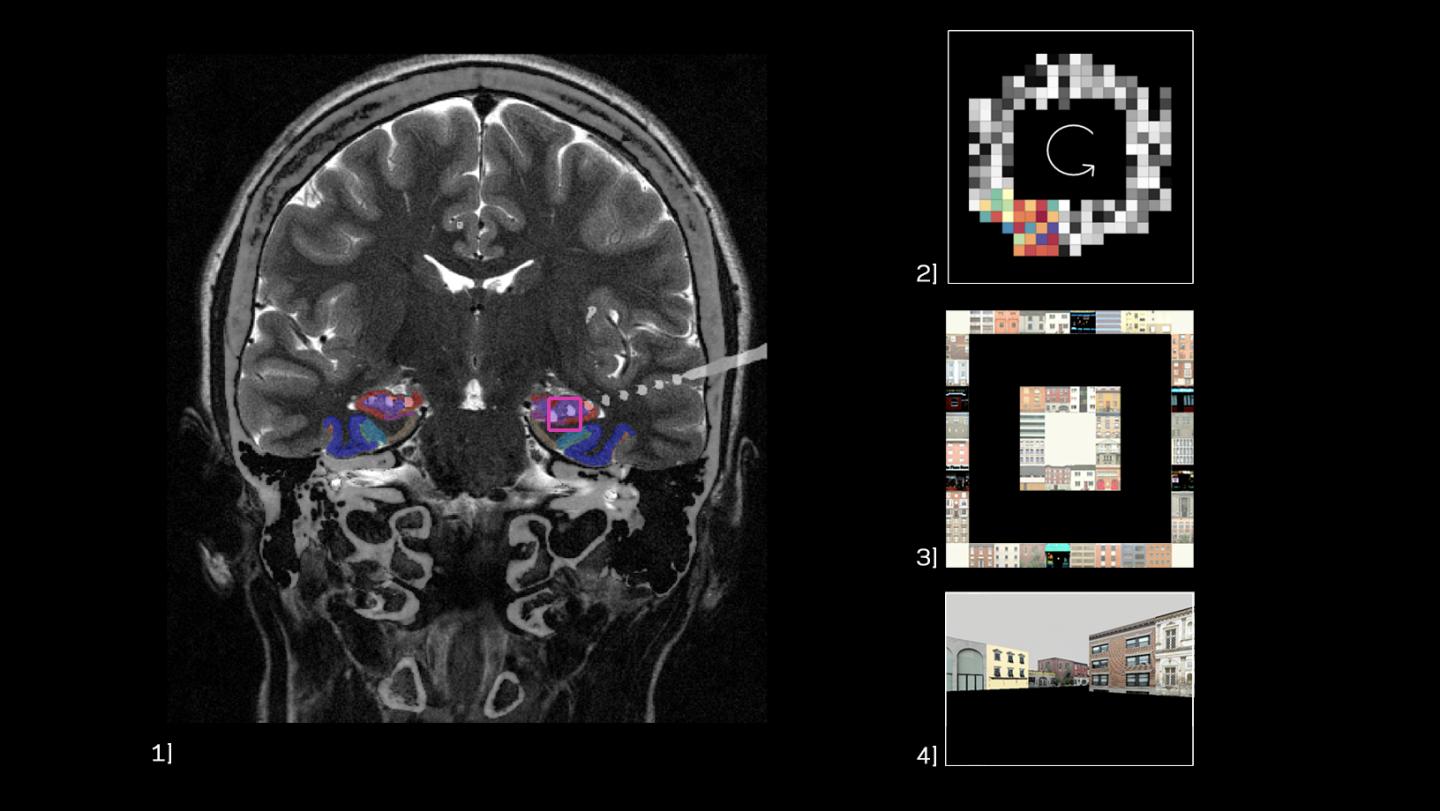

Phase precession in the human hippocampus.

image: <p>Phase precession in the human hippocampus. <p>01] Coronal T2 MRI scan merged with post-implantation CT scan showing location of electrodes (white circles) in the human hippocampus (red). <br>02] Heat map of spatial phase precession for one human hippocampal neuron. Each pixel represents a location in space in the virtual environment. Colors indicate the theta phase action-potentials occurred at as the subject moved through a particular location; precession is represented by the gradient of colors across space. <br>03] Overhead view of the virtual environment, showing the six navigation location goals. <br>04] First-person view of the virtual environment.</p> view more

Credit: Salman Ehtesham Qasim/Columbia Engineering